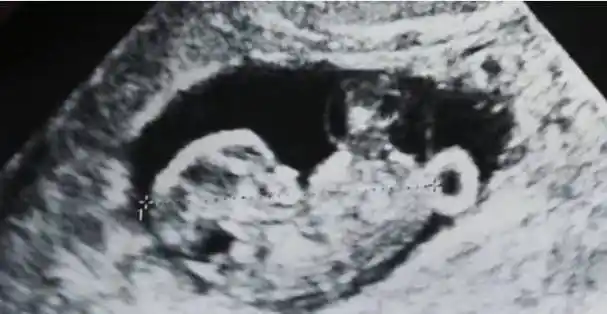

严屹宽庆生晒b超照,网友直呼又一个颜值宝宝将出生_孩子_照片_小王子